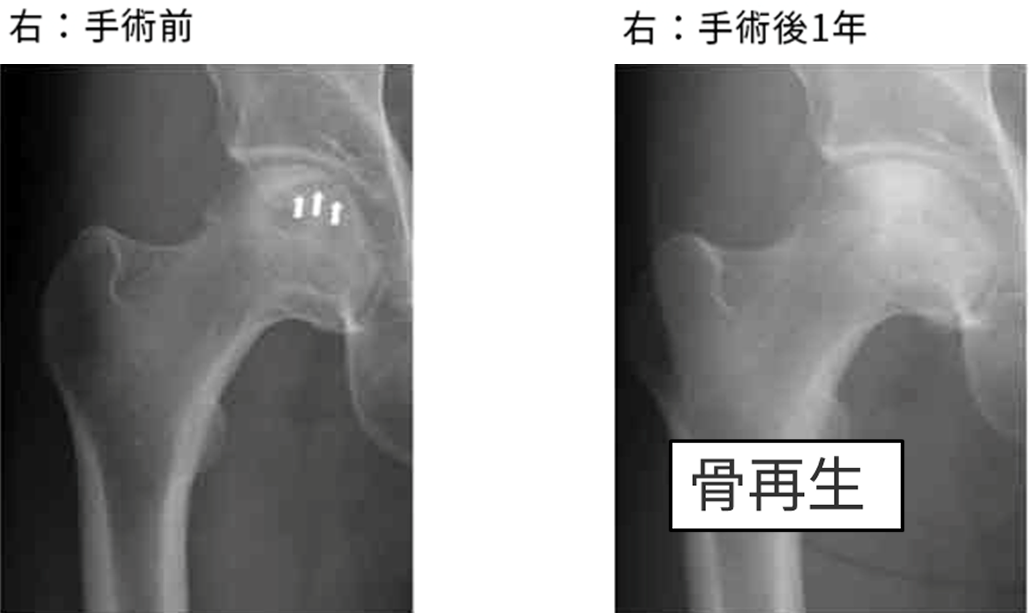

MRI検査

右Type C1 左Type C1

右Stage 2 左Stage 3A

壊死範囲が広いタイプでかかりつけ医から「いずれ人工股関節になる可能性が高い」と言われた

➡︎再生医療希望で受診 ➡︎両側の再生医療手術を施行

術前:骨頭内に左右とも骨折線のような黒い線(白矢印部分)が、骨頭の圧潰が進行中

術後1年:黒い線がなくなっており、骨頭内も白く、壊死部が再生